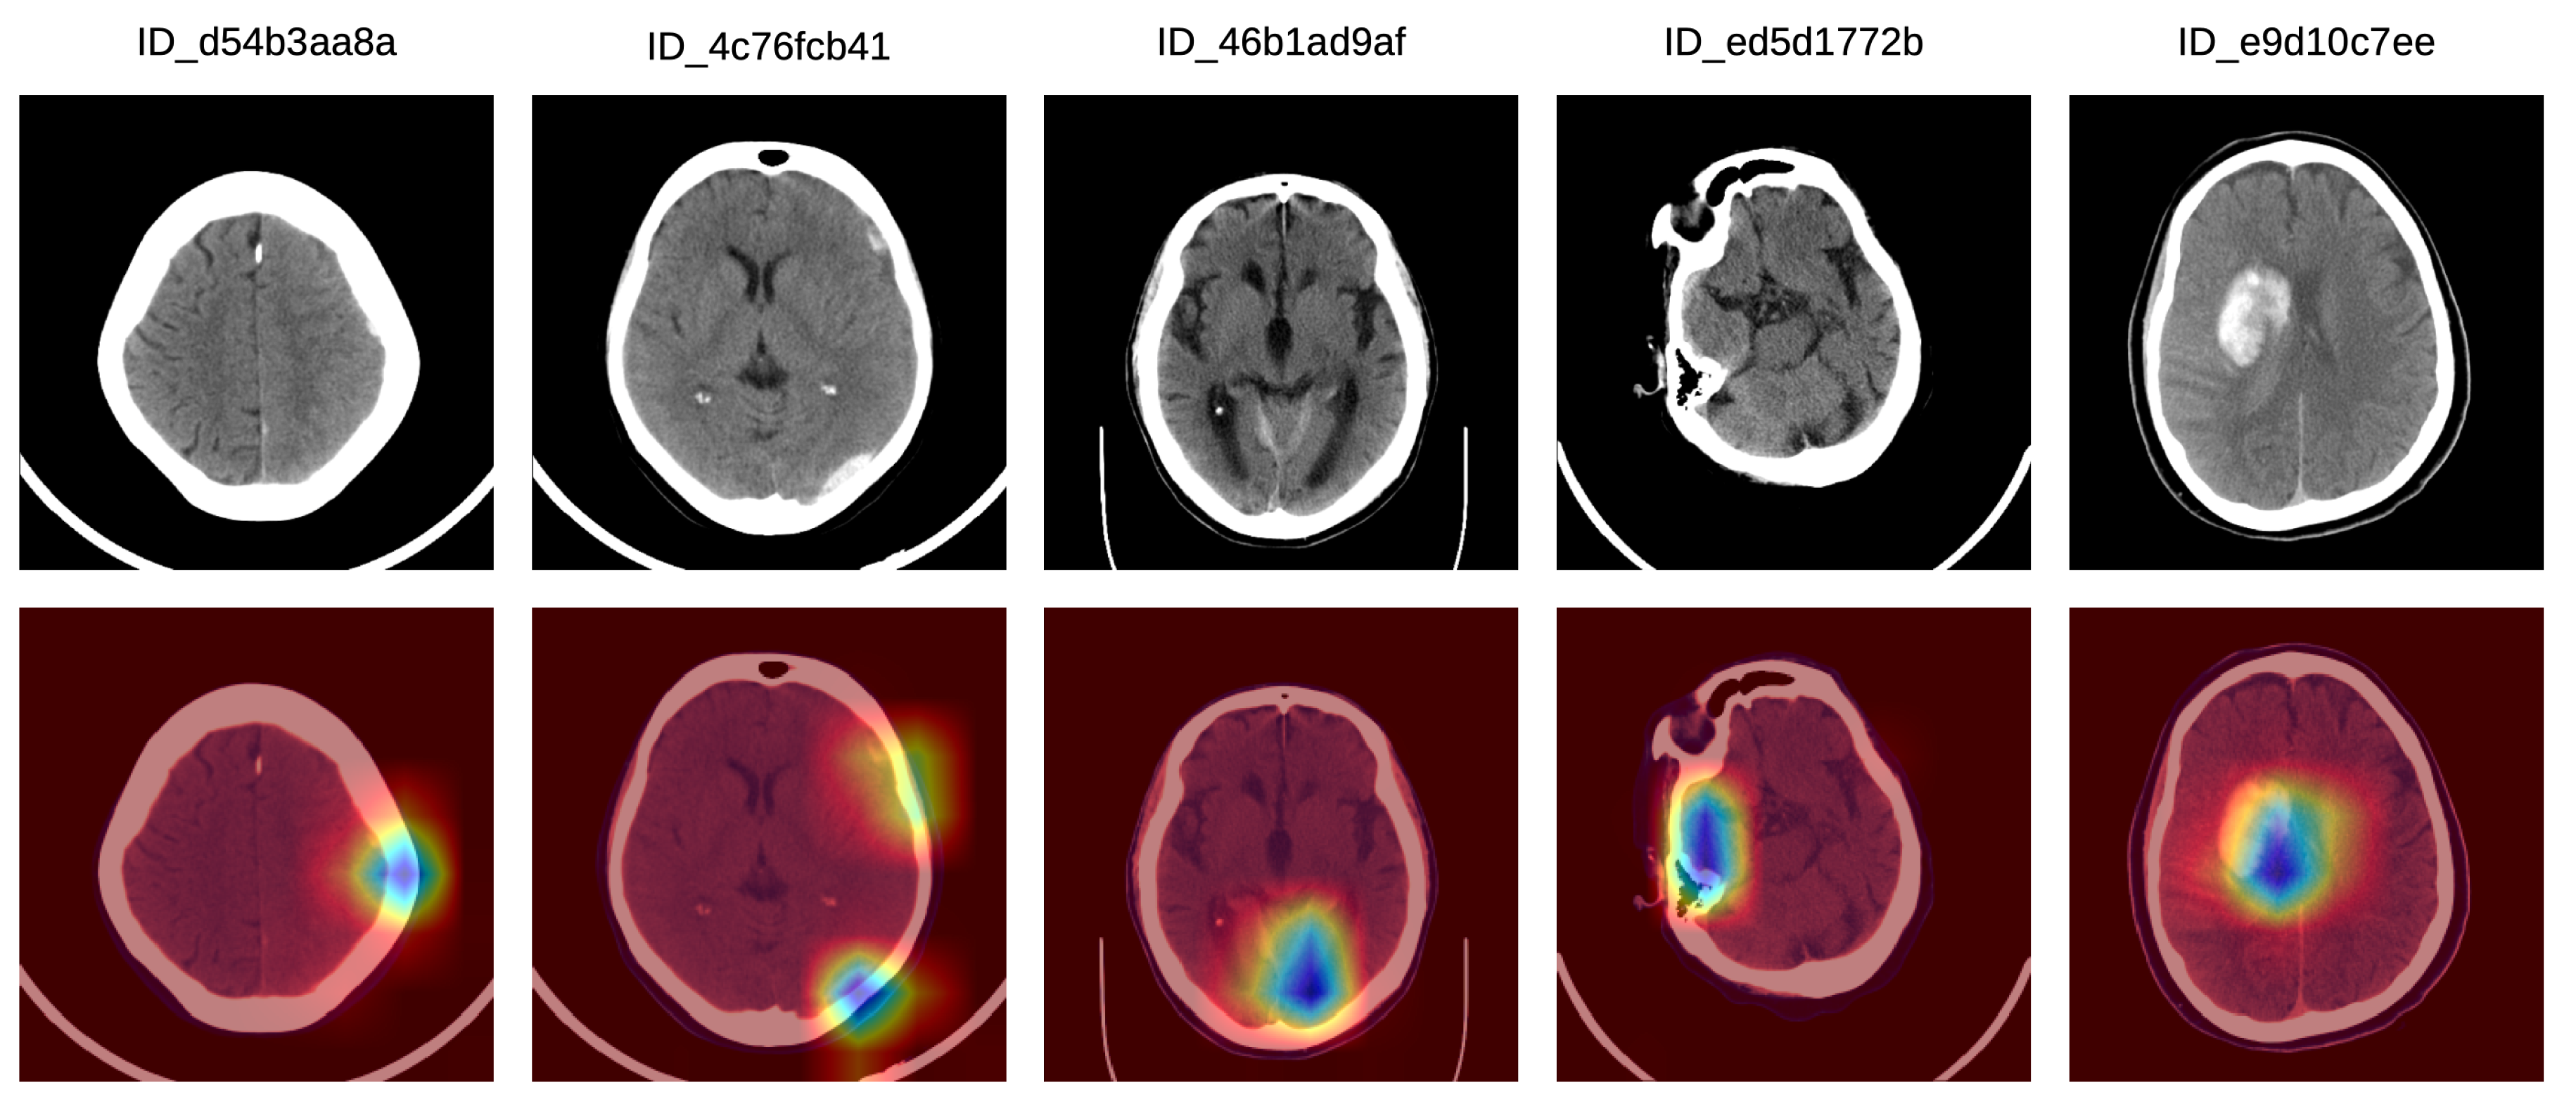

We applied some transformations to augment the dataset, generating multiple variations of the images in order to increase our model’s generalization capacity. Using the Albumentations library [51], the transformations that we chosen for data augmentation are: horizontal flipping, shifting, rotation, scaling and brightness adjustment. Some images before and after data augmentation are shown in Figure 2.

Figure 2.

Various image transformations (rotation, scaling, shifting, brightness changes) used for data augmentation. Each column contains random transformations applied to the corresponding CT slice displayed on the first row. Best viewed in color.